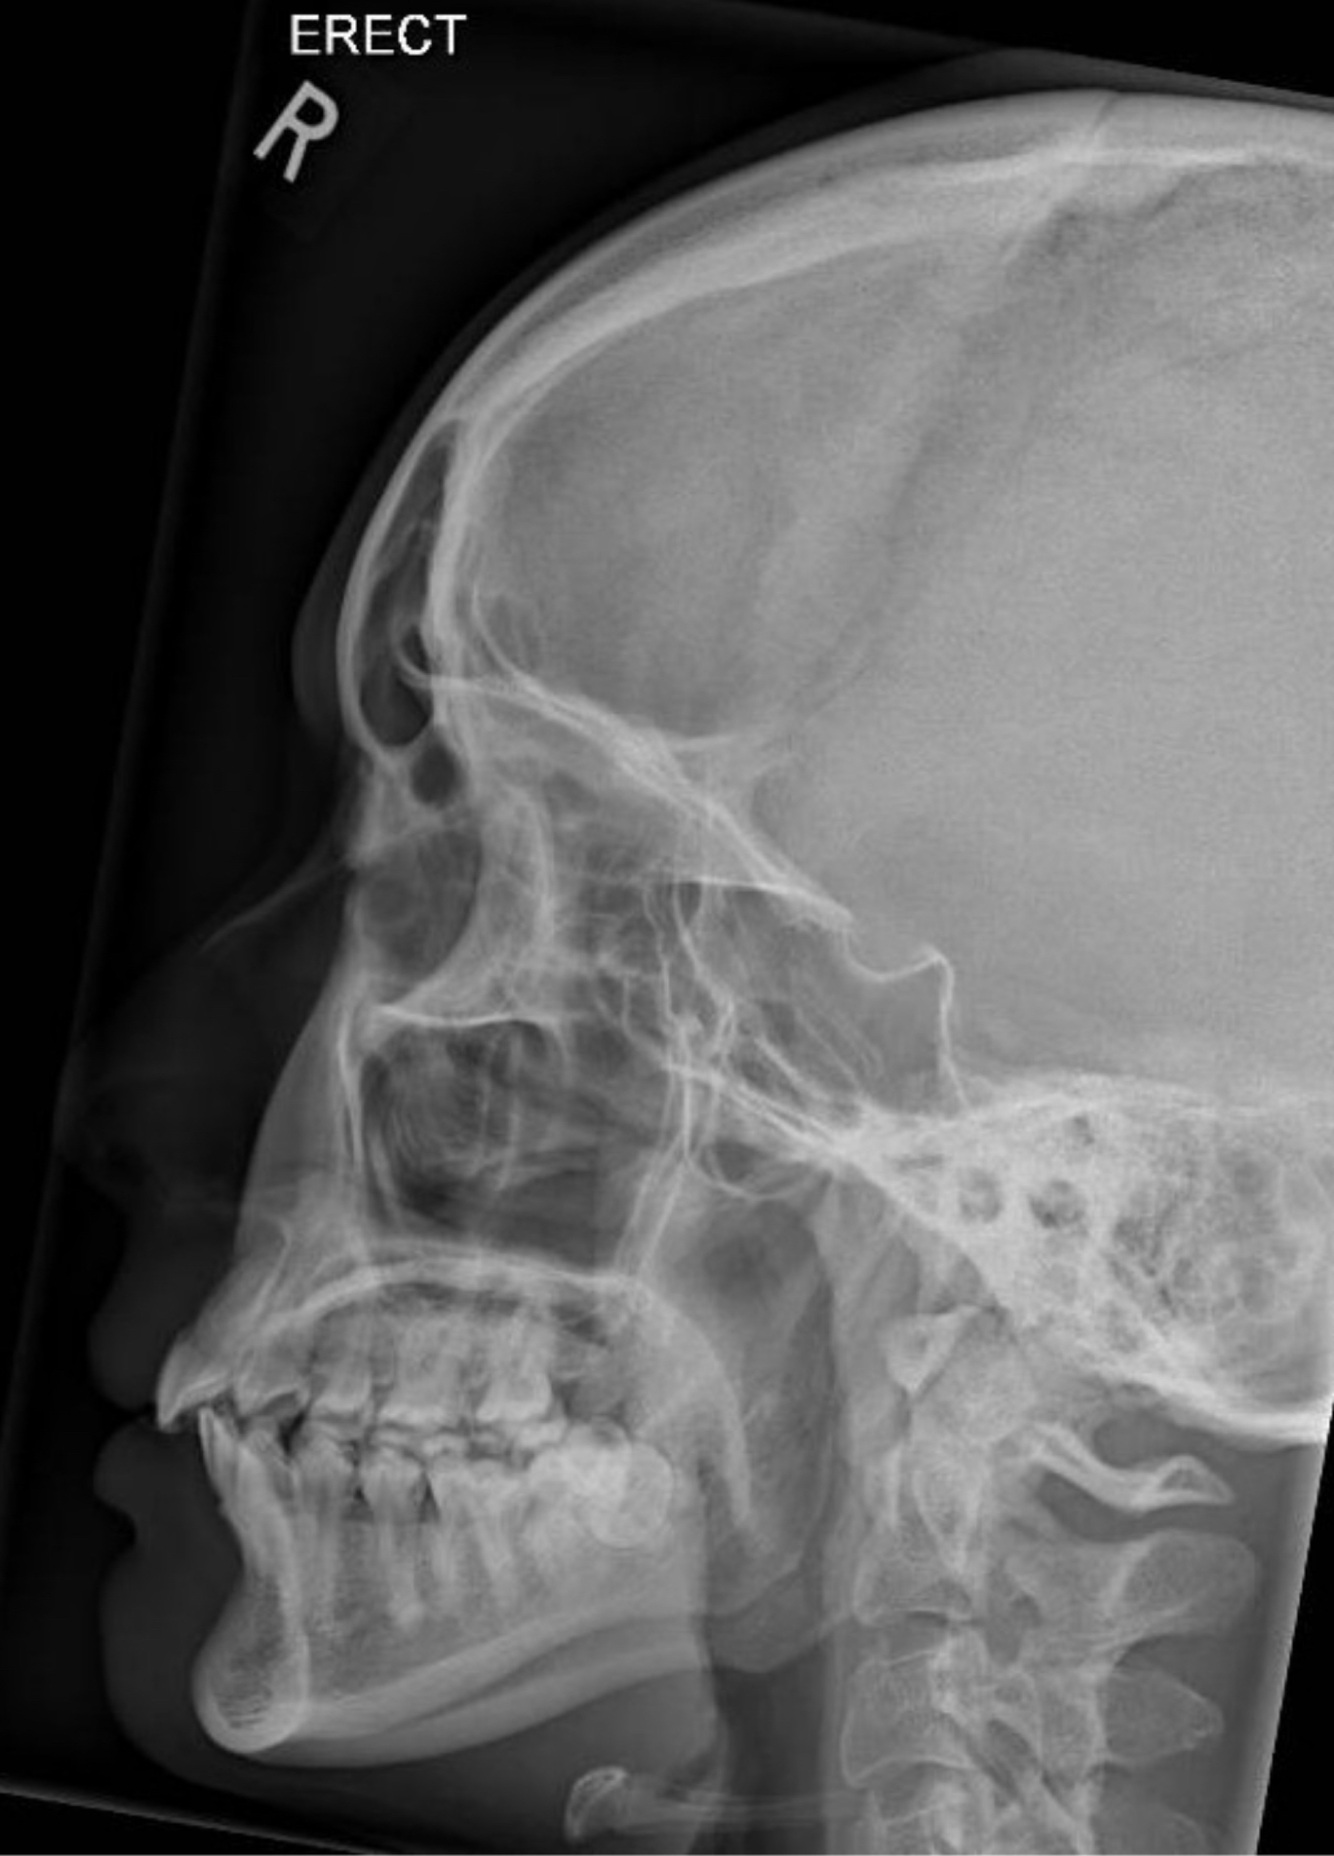

LATERAL Positioning

A

-MSP: II to IR

-IPL: ⟂ to IR

-IOML: II to long axis of IR (or ⟂ to front edge of IR)

-CR: 0.5-1” posterior to outer canthus

-SID: 40”

-Respiration: suspend

LATERAL Evaluation Criteria

-Proper Collimation

-All four sinus groups, best demonstration of sphenoid sinus

-No rotation or tilt

-SI orbital roofs

-SI mandibular rami

-Sella turcica in profile

-Brightness and contrast sufficient to visualize air fluid levels, if present